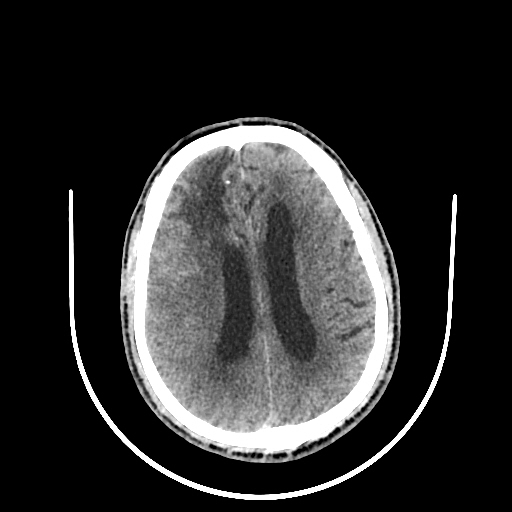

A 60 years old man with seizure since 12 years

Plan CT scan was done on 22 march 2016